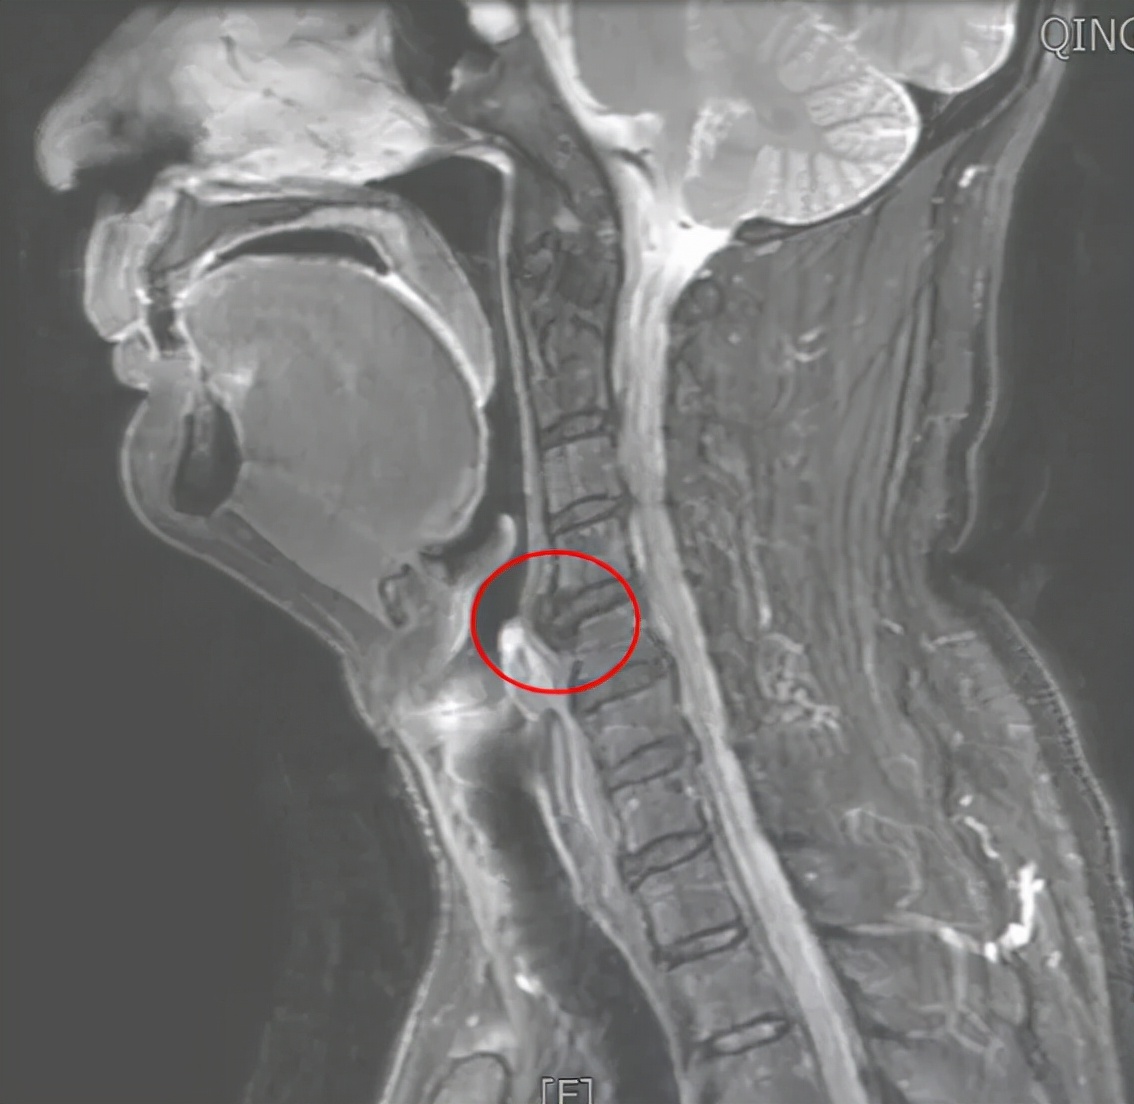

为一探究竟,团队最后决定对患者颈椎进行x光检查,果然有了重要发现:影像清晰地显示患者颈椎第56两节前方有巨大“鸟嘴状”骨赘,它是不是就是造成吞咽困难的罪魁祸首?

△CT与磁共振检查也显示颈椎第56两节前方巨大骨赘,且前方有水肿信号